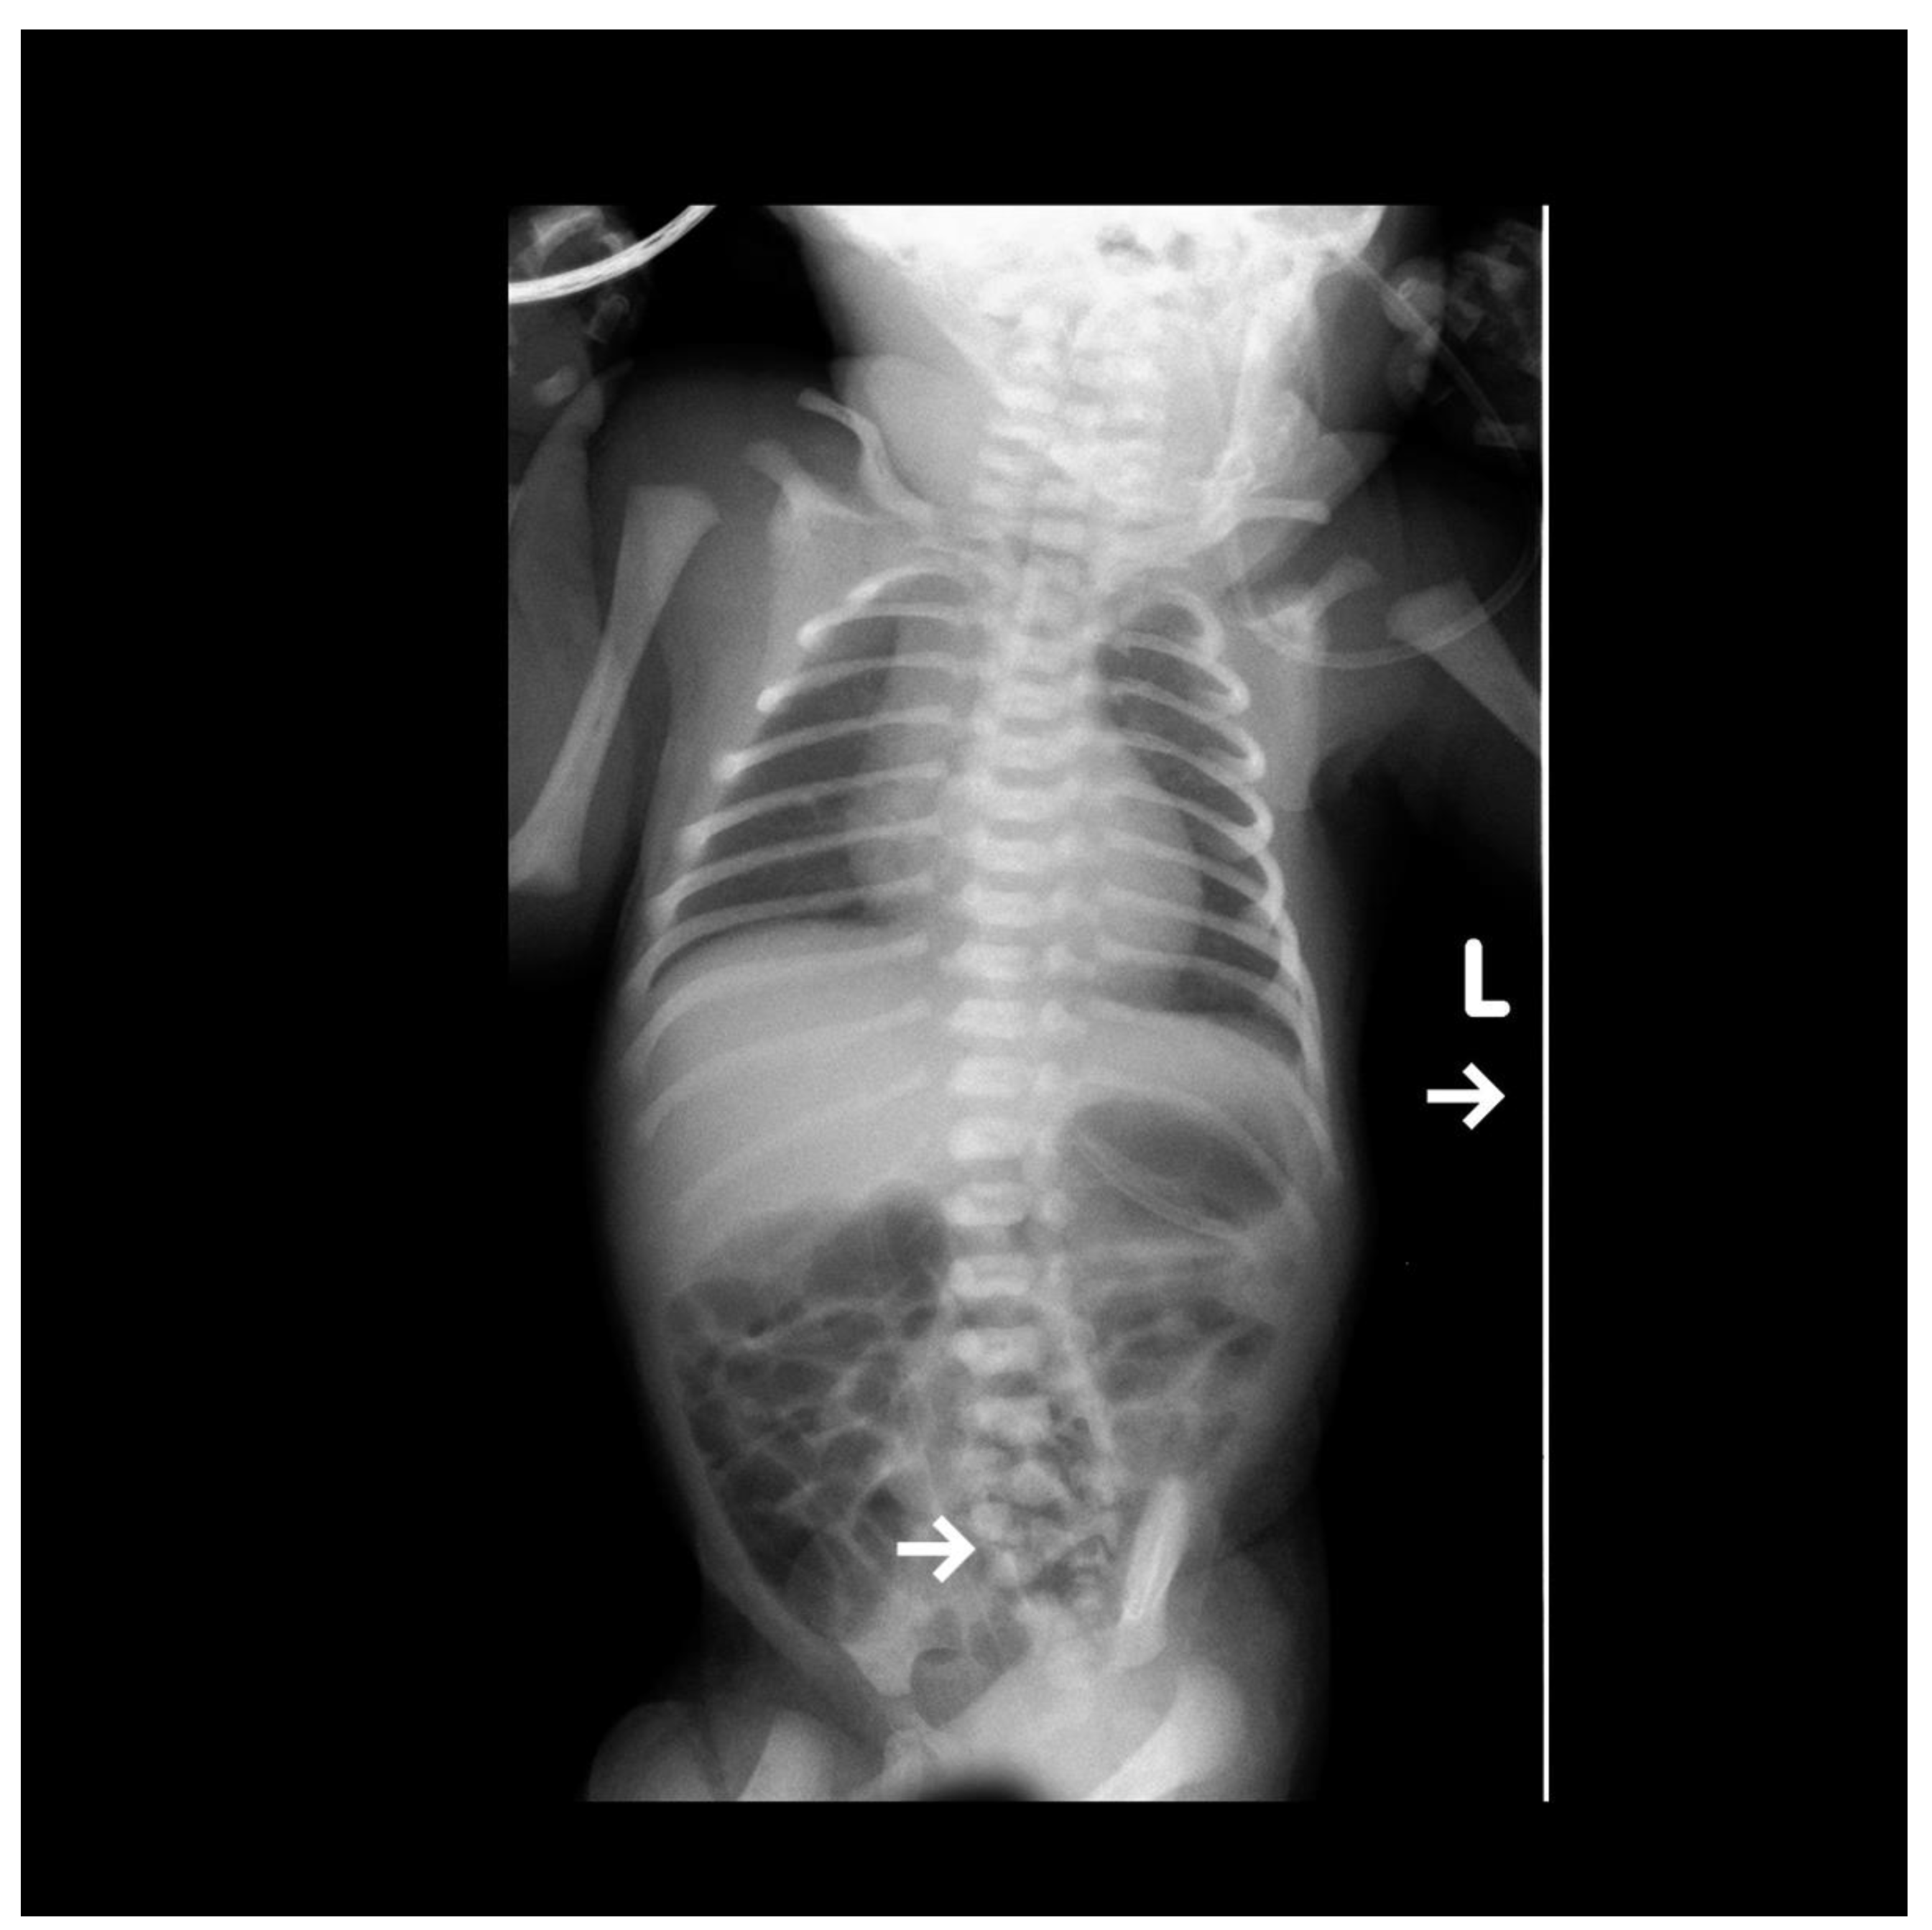

A female newborn was delivered via cesarean section (due to threatening fetal distress) with a diagnosed lumbar myelomeningocele and significant lower limb deformities after birth. The child was transported to our institute for further treatment. According to the medical record, the initial prenatal ultrasound was normal. In the 30th week of pregnancy, intrauterine growth restriction (IUGR) was diagnosed, and on the day of delivery, oligohydramnios and ventricular system enlargement of the central nervous system (CNS) were detected. On the first day of the patient’s stay, a set of tests was performed, including an anterior-posterior (AP) projection X-ray. The study shows a developmental defect of the lumbar-sacral spine (Figure 1).

Figure 1.

The visible AP projection X-ray shows bilateral small parenchymal consolidations in the upper lung fields. The vascular catheter ends at the level of Th11, projecting onto the liver. The end of the gastric probe is seen projecting onto the organ. Additionally, a clear developmental defect of the lumbar-sacral spine is visible, indicated by an arrow.